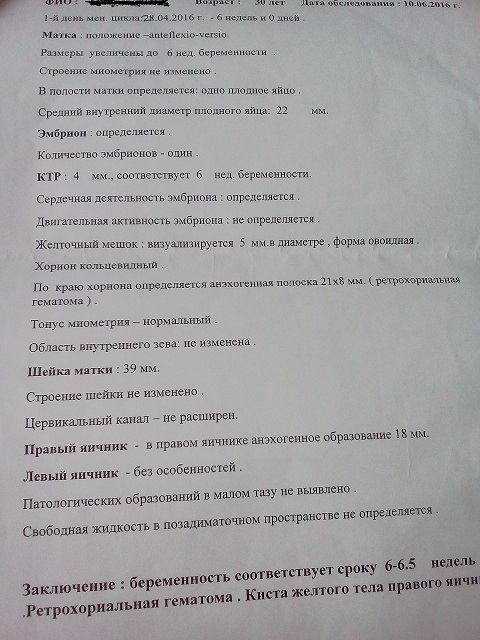

Сдавала я хгч для динамики,последний раз сдала 5 июня на 25-26 дпо-28952 мМе/мл. Так как сердце было не на месте,я сходила на УЗИ 10 июня. Поставили срок по М 6-6,5 недель. На фото видно заключение. Самое что пугающее это ретрохориальная гематома.Главное у меня,ттт,нет и не было выделений,живот болел и даже было ощущение каменения внизу живота недели 1,5 назад.Сейчас нет болей,ттт. Вчера побежала к дежурному врачу,не к своей попала. Она посмотрела меня,сказала матка мягкая,хоршая,тонуса нет. Типа такая ситуация у очень многих женщин и не все знают,так как не ходят на УЗИ так рано. Направила на дневной стационар с 14 июня. Сказала,если закровите,то скорую вызывайте.А так,типа может она у вас рассосется. И все,сказала,будет хорошо. Девочки поддержите хорошими примерами,пожалуйста.Сейчас дома,соблюдаю постельный режим по возможности,пью Магний Б6,утрик 200 на ночь,фолька,папаверин если будет тянуть живот. И на первой фото,где видно эмбриончик,там внизу черная полоска-это и есть гематома?Подскажите,кто может знает. На второй фото это гематома с размерами. Спасибо всем заранее!